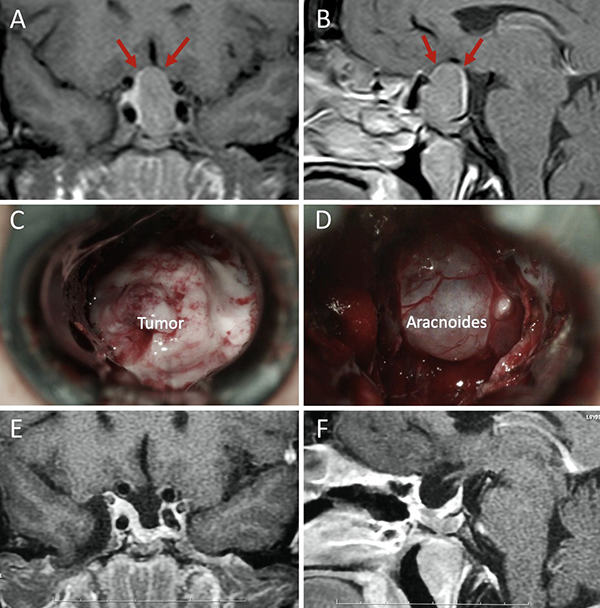

Una clasificación clásica de los adenomas es según su tamaño. Se los clasifica en microadenoma <10 mm (fig. 2), macroadenoma >10 mm (fig. 3), y adenoma gigante > 30 mm (fig. 4). Esta clasificación es importante ya que los índices de remisión están ligados al tamaño del adenoma y también su recidiva.12

Figura 4: Adenoma gigante. A-B: RM preoperatoria; C-D: RM postoperatoria.

El techo de la fosa pituitaria está constituido en condiciones normales por un máximo de 2 estructuras: duramadre (diafragma selar) y aracnoides.65,66 En condiciones patológicas, cuando existe un adenoma hipofisario, éste empuja hacia arriba a la glándula. De este modo, la interfase entre el tumor y el LCR se encuentra constituida por un máximo de 3 elementos: glándula, duramadre y aracnoides. Cabe destacar que la aracnoides es el único elemento constante. A los elementos que constituyen esta interfase el equipo de Tucumán los denominó “barrera selar”.11,60

Existen 3 subtipos de barrera selar según los hallazgos intraoperatorios, luego de resecar el tumor:

Un factor interesante de este novedoso concepto es que el tipo de barrera puede evidenciarse en la RM preoperatoria. De este modo, existen 3 subtipos de barrera selar según la radiología:

Los pacientes con una barrera débil tienen mayor riesgo de fístula intraoperatoria de LCR. La barrera fuerte es un factor protector de fístula de LCR.11,60

Figura 8: Barrera selar débil. A-B) RM preoperatoria; C-D) Hallazgos intraoperatorios. E-F) RM postoperatoria. Flechas rojas: interlínea < 1mm. Tomado de Campero A, Villalonga JF, Basso A. Anatomical risk factors for intraoperative cerebrospinal fluid leaks during transsphenoidal surgery for pituitary adenomas. World Neurosurg. 2019;124:346-55.